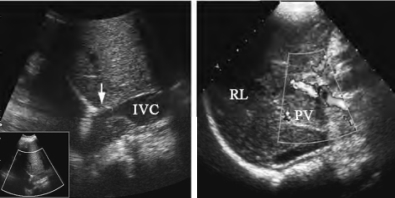

图23-16 原发性肝癌声像图

高回声型肝右叶大部为周缘有晕环的高回声区占据,内部回声不均匀

图23-17 肝癌声像图

伴下腔静脉、门静脉内癌栓

1.肝脏内局限性异常回声区,边界清楚或不清楚,轮廓比较规则 其回声类型可有:低回声型(图23-15)、等回声型、高回声型(图23-16)、混合型等。混合型可为强弱不等回声,不均匀分布,或为内有液化坏死呈不规则无回声区。小肝癌多为低或等回声型,结节型及巨块型肝癌可为高回声或混合回声型。

2.病变与周围肝组织间多见“晕环征”,显示为低回声带(图23-16)

6.转移征象 门静脉、下腔静脉内癌栓(图23-17),卫星癌结节,淋巴结肿大等征象。